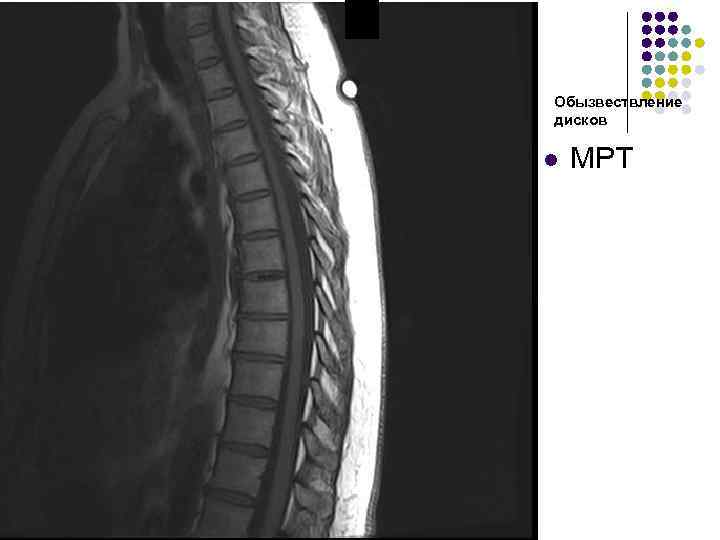

Обызвествление дисков l МРТ

Обызвествление межпозвоночного диска